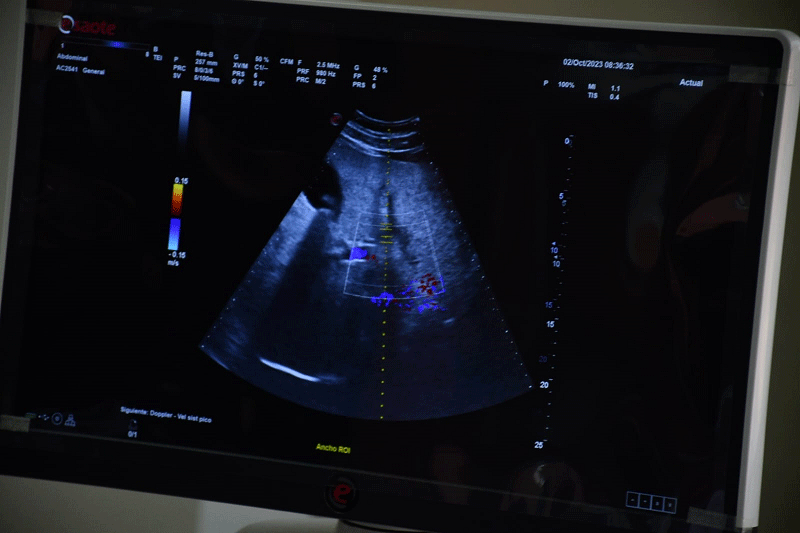

El Gobierno Autónomo Municipal de Santa Cruz de la Sierra realizó la entrega de 14 ecógrafos estacionarios de última generación para los centros de salud del primer nivel. Los pacientes podrán acceder a los servicios de ecografía abdominal, obstétrica, ginecológica entre otras.

El ecógrafo es un equipo de ultrasonido de diagnóstico necesario en medicina general para la realización de exámenes de ecografía de acuerdo al nivel de complejidad en establecimientos de salud de primer nivel. Estos equipos ayudan al desempeño de los profesionales en la salud en el servicio de imagenología.

En total son 14 ecógrafos con una inversión de Bs 3,780,000 millones y serán distribuidos en las cuatro redes de salud de la urbe cruceña. Además. se tiene programado seguir con la dotación de insumos y reactivos.